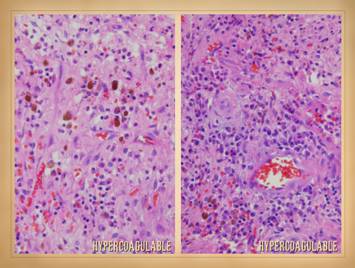

In these cases, all wounds are chronic, of long duration, and getting some basic topical wound care and treatment for their disease.  Left top:  lupus with anticardiolipin hypercoagulability, zones of granulation tissue, zones without, small active infarcts at wound edges, persistent inflammation.  Left bottom:  rheumatoid, active wound module of deeper musculoskeletal structures, but no wound healing in subcutaneous panniculus, active persistent erosions at wound margins, but periwound inflammation is controlled.  Left inner top:  rheumatoid with coincidental atherosclerosis, stable areas mixed with erosive areas, wound healing in musculoskeletal structures but none in the adipose.  Left inner bottom:  lupus-rheumatoid-mctd, stable wounds, no periwound inflammation, healing of musculoskeletal structures but not of adipose.  Center lower:   polyarteritis, failed wound module, recurrent acute necrosis.  Right inner:  lupus with anticardiolipins, failed epithelialization, stalled edges, limited contraction, weak angiogenesis/granulation.  Right top:  rheumatoid and hypercoagulable, wound module present at musculoskeletal base but not in subcutaneous fascias, no contraction nor epithelialization, small surface infarcts even absent periwound inflammation.  Right bottom:  rheumatoid, persistent unchanged wound over a few weeks of observation and care, weak expression of wound module elements, failed epithelialization and stalled edges.

This slide shows the features of chronic and late ulceration.  In chronic ulcers, the original cause of the disease has subsided, and what is left is just the anatomical defect.  To the extent that the disease is still active, there may be ongoing slow progression of the wound or persistence of related findings and general symptoms.  To the extent that the disease is affecting wound repair, or that the ulcer has entered a physiological and pathological state of chronicity, then healing may be retarded or absent.  When looking at the wounds during these latter chronic phases, what you will mainly see is just a generic chronic wound.  Specific common features to observe include the following.  Persistent inflammation:  If primary disease is quiet, then inflammation may subside, but most such wounds are in a state of chronic inflammation until treatment brings it under control.  Some of it is likely to be a persistent acute inflammation due to lack of care.  However, acute inflammation is a good stimulus to maintain the pathological chronic inflammation of the disease, and these wounds rarely break out of their pathological attractor until both the wound and the general disease are explicitly treated.  Progressive ulceration:  As chronic wounds, most of these ulcers persist as is, often indefinitely.  However, after prolonged periods of stability they can also get better or get worse.  Many patients describe prior ulcers which healed spontaneously, typically taking months, and healing with treatment is the goal of all of this.  To the extent that primary disease or chronic inflammation in the wound is sustained, there may be slow progressive necrosis or ulceration.    Sudden rapid progressive ulceration and enlargement is a good indicator of resurgence of the primary disease.  Retarded wound module, mixed wound module, and chaotic behavior:  The immunopathic ulcers have a duality of wound effects.  Their afferent effect on the wound is to make the ulcer.  Their efferent effect is to keep it from healing.  There are very few types of pathology that can arrest the wound module, and active auto-immunopathy is one of them.  For most patients, wound healing is mixed, both in space over the surface of the wound, and in time from one observation to another.  There may be qualitatively normal proliferation in some areas.  There may be areas of appropriate suppression of wound healing by acute inflammation.  There can be zones where the wound module is very weak or inactive due to the primary effects of the auto-immunopathy, the effects of persistent allied disease states such as hypercoagulability, and the effects of wound chronicity.  There can be intermittent areas of new ulceration due to persistent chronic disease activity.  Even when the wounds look normal at first glance, it is rare that such wounds are quantitatively normal with normal kinetics.  One of the hallmark features of wound chronicity is chaotic behavior (as explained in subsequent slides) in which the wound may wax and wane but never makes any real progress.  Pain & symptoms:  There are only a handful of generic causes of pain (mechanical, neuropathic, ischemia, cancer, etc.), and inflammation is one of them.  Because these ulcers represent an inflammatory pathology, pain is a common feature.  For those who have a concomitant thrombotic or micro-occlusive disorder, the pains are even worse.  Other symptoms of the primary disease, and secondary symptoms or disabilities related to what is ulcerated are also part of the picture of the chronic stages of auto-immune ulceration.